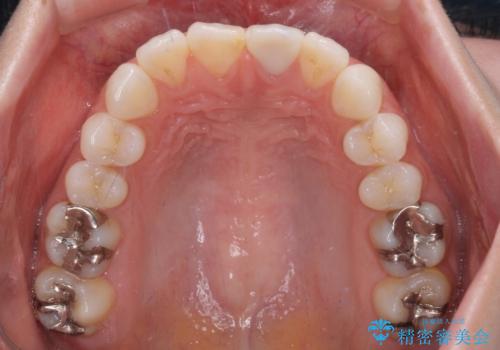

前歯1歯でのオールセラミッククラウンでは、オーダーメイドタイプのクラウンを選択していただき、周辺の歯と色調を合わせるようにするのですが、今回は既製タイプを選択されました。